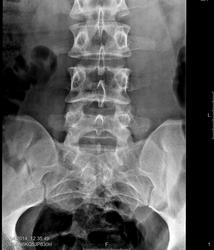

Пол пациента: Мужской пол Тип патологии: Врожденная патология Область исследования: Скелетно-мышечная система Методы исследования: Rg Есть ли здесь аномалия развития? ID:36884 Tue, 08/04/2014 - 14:31 #1 Doc84 Offline Last seen: 11 years 6 months ago Joined: 05.03.2014 - 15:21 Posts: 209 Spina bifida posterior крестца. Снимки у вас шикарные Tue, 08/04/2014 - 21:31 #2 И.Бондаренко Offline Last seen: 5 days 11 hours ago Joined: 13.09.2011 - 22:55 Posts: 9206 Doc84 wrote: Spina bifida posterior крестца. Поддерживаю. Wed, 09/04/2014 - 00:47 #3 Nobody Offline Last seen: 11 years 2 months ago Joined: 15.03.2014 - 20:29 Posts: 2013 Doc84 wrote: Spina bifida posterior крестца. Снимки у вас шикарные Прошу прощения, но с учётом качественных снимков, хотел заметить, что кишка там красиво наслаивается... точно на якобы аномалию эту.) "Лишь утратив всё до конца, мы обретаем свободу." F.C. Wed, 09/04/2014 - 15:10 #4 Doc84 Offline Last seen: 11 years 6 months ago Joined: 05.03.2014 - 15:21 Posts: 209 Nobody wrote: Doc84 wrote: Spina bifida posterior крестца. Снимки у вас шикарные Прошу прощения, но с учётом качественных снимков, хотел заметить, что кишка там красиво наслаивается... точно на якобы аномалию эту.) Наверное вы правы... Глаз мне недостаточно "набили" в свое время )) Wed, 09/04/2014 - 17:47 #5 atexta Offline Last seen: 2 years 11 months ago Joined: 08.02.2014 - 18:41 Posts: 4842 По снимку всегда смотрю, есть ли сращение задних дужек в остистый отросток Не нам судить…

Spina bifida posterior крестца. Снимки у вас шикарные

Прошу прощения, но с учётом качественных снимков, хотел заметить, что кишка там красиво наслаивается... точно на якобы аномалию эту.)

По снимку всегда смотрю, есть ли сращение задних дужек в остистый отросток